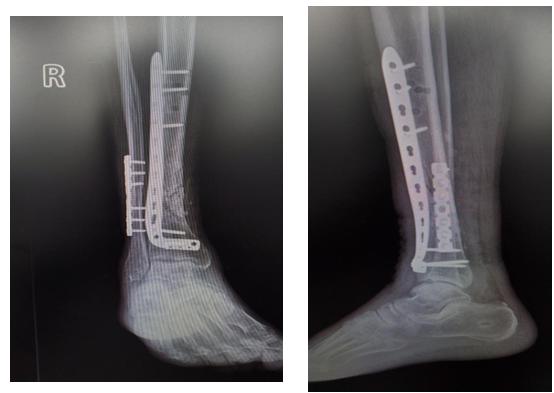

患者吴某,男性,74岁,因外伤致右胫腓骨开放粉碎骨折,右胫骨部分骨缺损7周入住市中心医院骨二科。入院诊断:右胫骨骨折骨水泥占位术后;右胫骨骨折外固定架固定术后;右腓骨骨折术后。急诊行胫骨开放骨折清创复位克氏针内固定+骨水泥占位+外固定架固定、腓骨骨折切开复位内固定、创面负压吸引术,术后定期伤口换药,预防感染等治疗。近日,在腰硬联合麻醉下行右胫骨骨水泥取除、骨折切开复位内固定、髂骨取骨植骨术,术中取部分软组织行冰冻病理切片,以高倍视野下中性粒细胞计数少于5个为标准排除感染,骨缺损处植入自体松质骨及人工骨混合物,缝合诱导膜;胫前部分切开置入内固定,术后患者伤口愈合良好。

I 期骨缺损处在体内通过骨水泥占位

II 期采用自体松质骨及同种异体骨移植+内固定术